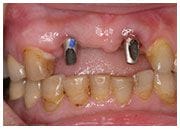

植牙過程

治療中